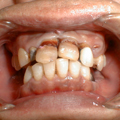

■重度の歯周病

しかし、歯肉炎を放置していると歯を支えている歯槽骨(しそうこつ)にまで炎症が拡大し、歯肉と歯槽骨を含めた歯周炎となります。

さらに歯周炎がひどくなると歯ぐきから膿がでたり、歯がぐらついたりしてきますが、そのような状態は一般的に歯槽膿漏(しそうのうろう)と呼ばれています。

最近の研究では、歯周病は歯ぐきの病気だけではなく、心臓疾患や吸器疾患や早産を引き起こす危険性を増加させると報告されており歯周病の予防と治療が全身の健康にも良い結果をもたらすと考えられています。